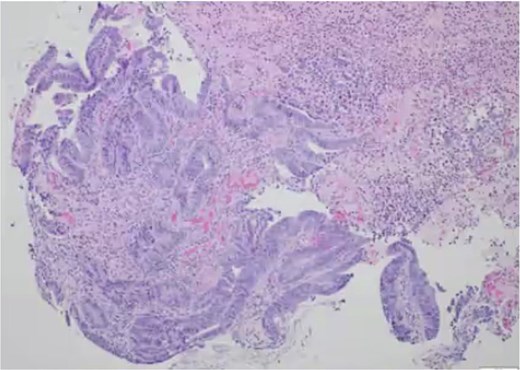

Histopathology report of the resected rectum confirmed moderately differentiated invasive colonic adenocarcinoma 1.5 cm pT2N0 (0/18 lymph nodes) (Fig. 3). The distal margin was focally positive for low-grade dysplasia. Pathology results were reviewed with the patient at outpatient follow up. An intersphincteric proctectomy with levatorplasty was scheduled and a carcinoembryonic antigen (CEA) and CT chest was ordered. CEA was elevated at 13.4 one month following his LAR. CT chest showed a suspicious lung mass, prompting a positron emission tomography (PET) scan. Although the lung mass was no longer present on the PET scan, it did demonstrate metastasis to the right hepatic lobe, for which a wedge resection was performed.

Pathology slide of rectal biopsy. Pathology of rectal biopsy demonstrating tubulovillous adenoma with focal high-grade dysplasia.

This patient’s pathology revealed a tubulovillous adenoma with focal high-grade dysplasia and adjacent ulceration, ultimately classified as a moderately differentiated invasive colonic adenocarcinoma with invasion into the muscularis propria (Fig. 3). About 18 regional lymph nodes were examined, all of which were negative for metastatic disease (pN0), exceeding the recommended minimum of 12 nodes for accurate pathologic staging. Although T2N0 colorectal tumors generally carry an excellent prognosis, a subset of biologically aggressive cancers has been shown to undergo early hematogenous dissemination with relative bypass of the lymphatic system [18, 19]. The presence of distant metastases in this patient despite adequate lymph node sampling and negative nodal involvement suggests either high-risk pathologic features or an intrinsically aggressive tumour phenotype with a preferential hematogenous spread. Performing a colonoscopy on this patient despite negative imaging findings on this patient was critical.